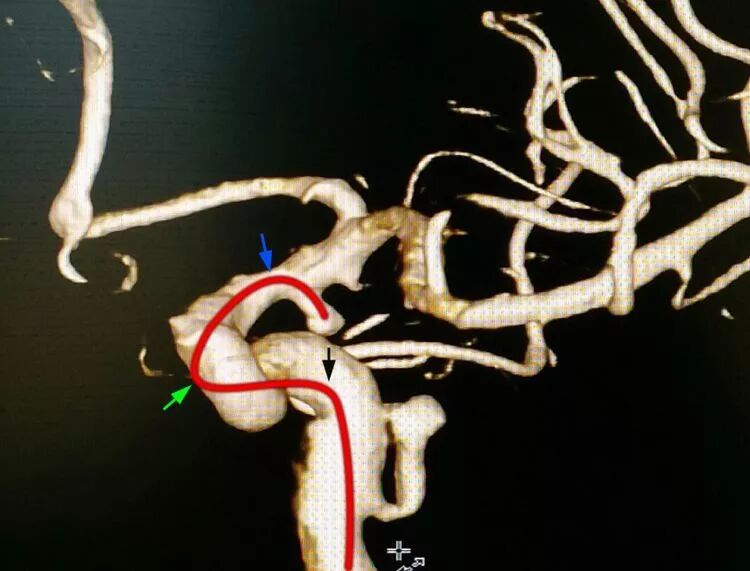

后交通动脉瘤,朝外下方生长,欲把微导管头塑成C形,需塑两个弯儿,第一个弯儿(蓝箭头)顺应动脉瘤体和颈内动脉C1段的成角,第二个弯儿(绿箭头)顺应颈内动脉虹吸弯前膝的弯度,更近心端的弯儿(黑箭头)不用塑形,是微导管在载瘤动脉内的自然成形